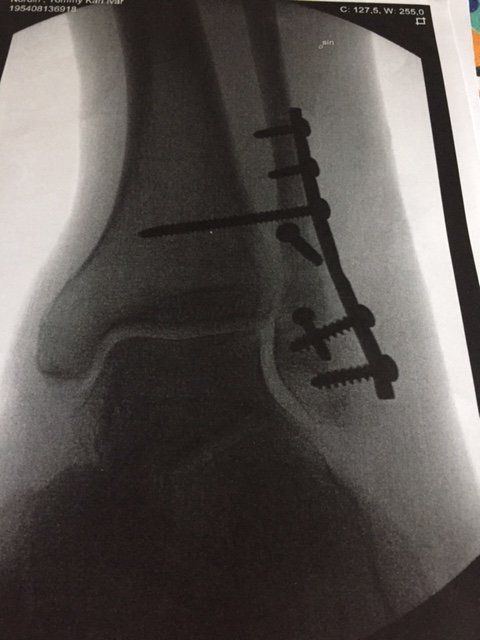

Bröt ankelbenet (fibula, fraktur Weber B) för en vecka sedan i Obergurgl. Blev opererad hemma i Sverige och fick en platta ditskruvad plus en skruv genom brottstället samt ett par märlor från ankelbenet till foten (syndesmosen).

Gjorde det 2017 i januari v:2 cyklade på Mallis i april v:17. Inga problem med skidåkningen nästa vinter, behövde inte en trycka ut pjäxorna.

F161D4F7-7D6B-4383-893B-34651E026720.jpeg